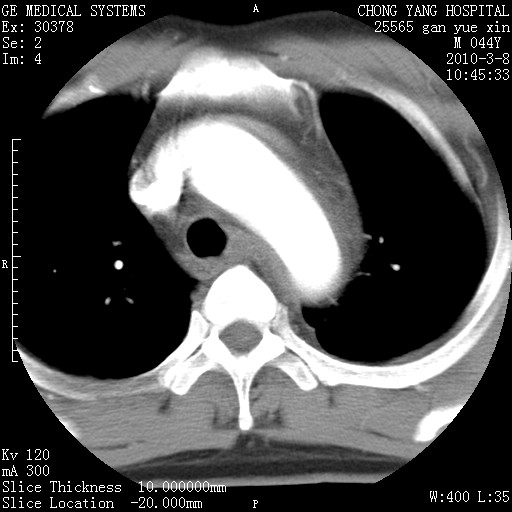

标题: CT24940:主动脉增强,典型病例。 [打印本页]

标题: CT24940:主动脉增强,典型病例。

夹层动脉瘤。

动脉夹层

夹层动脉瘤,典型

主动脉夹层。

动脉夹层的分型:

⒈debakey分型:根据主动脉夹层累及部位,分为三型:ⅰ型:原发破口位于升主动脉或主动脉弓部,夹层累及升主动脉、主动脉弓部、胸主动脉、腹主动脉大部或全部,少数可累及髂动脉。ⅱ型:原发破口位于升主动脉,夹层累及升主动脉,少数可累及部分主动脉弓。ⅲ型:原发破口位于左锁骨下动脉开口远端,根据夹层累及范围又分为ⅲa,ⅲb。ⅲa型:夹层累及胸主动脉。ⅲb型:夹层累及升主动脉、腹主动脉大部或全部。少数可累及髂动脉。

⒉stanford分型:a型:夹层累及升主动脉,无论远端范围如何。b型:夹层累及左锁骨下动脉开口以远的降主动脉。

夹层动脉瘤,少量胸水

夹层动脉瘤;左侧少量胸腔积液。

典型主动脉夹层。